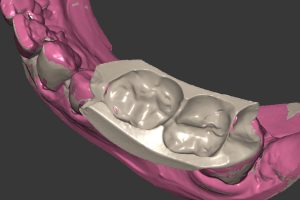

- Ryc. 22_Filar protetyczny na modelu z maską dziąsłową, strona okluzyjna.

- Ryc. 23_Filar protetyczny na modelu ze zdjętą maską dziąsłową.

Mimo, że w większości wypadków łącznik nie wymaga korekt, to zdarza się, że klinicznie korygowane są pewne jego elementy (np. położenie stopnia dla korony). Na kluczu do pozycjonowania przenosi się łącznik i ustawia w platformie protetycznej implantu oraz przykręca w ustalonej pozycji śrubo- krętem dynamometrycznym. Następnie pobierany jest drugi wycisk z indywidualnie przygotowanym transferem wyciskowym na łyżce zamkniętej, tym razem z poziomu łącznika. Takie postępowanie ma wiele zalet: pozwala na uniknięcie błędu pozycjonowania stożka w platformie protetycznej implantu, umożliwia dokładne opracowanie powierzchni stycznych przyszłej korony w stosunku do zębów sąsiadujących oraz dokładnie odwzorowuje stan tkanek miękkich i ich kompresję po przykręceniu łącznika. Następnie, po pobraniu wycisku, do łącznika przykręcany jest drugi analog implantu, łącznik jest osadzany w wycisku i odlewany w laboratorium kolejny model z maska dziąsłową. Tak więc laboratorium ma do dyspozycji 2 modele robocze, które jednak mogą nieznacznie różnić się między sobą. Na drugim modelu przygotowywana jest ostatecznie korona. Łącznik jest skanowany, następnie projektowana jest w systemie CAD/ CAM czapka korony, wycinana z bloczku cyrkonowego, synteryzowana i następnie odsyłana do ceramisty w celu napalenia warstwowo porcelany dentystycznej. Gotowa praca (łącznik i korona) przesyłana jest do kliniki celem ostatecznego osadzenia w jamie ustnej pacjenta podczas kolejnej wizyty.